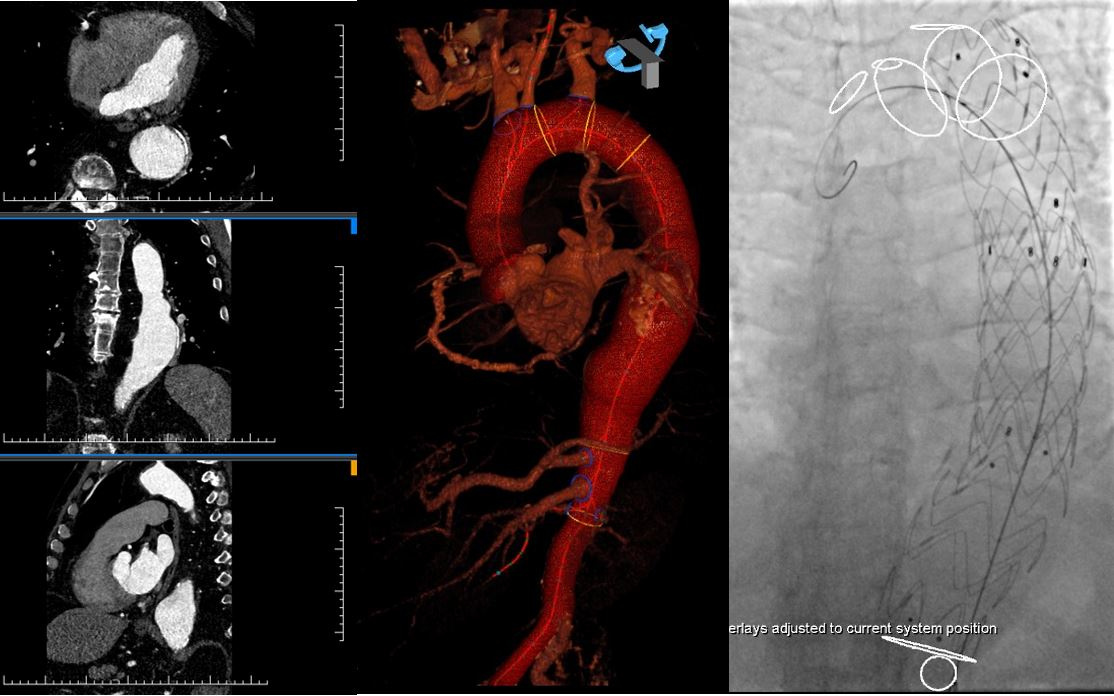

Pacient s výduťou brušnej aorty a panvových tepien ošetrený miniinvazívne cez malý rez v slabine pomocou špeciálnej cievnej protézy, ktorá umožňuje zachovať tok aj do vnútornej panvovej tepny. Pomocou 3D navigácie a fúzie s CT obrazom sa skrátil celkový čas implantácie a výrazne zredukovala radiačná dávka aj objem podanej kontrastnej látky.